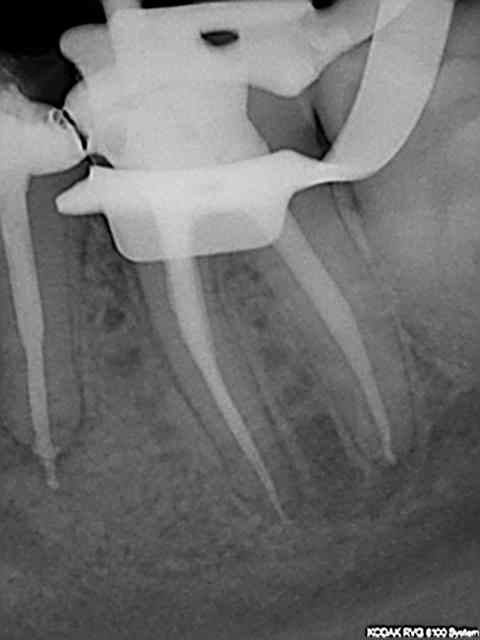

R31 mnpgen - Eugenol

R34 qggho9 - Eugenol